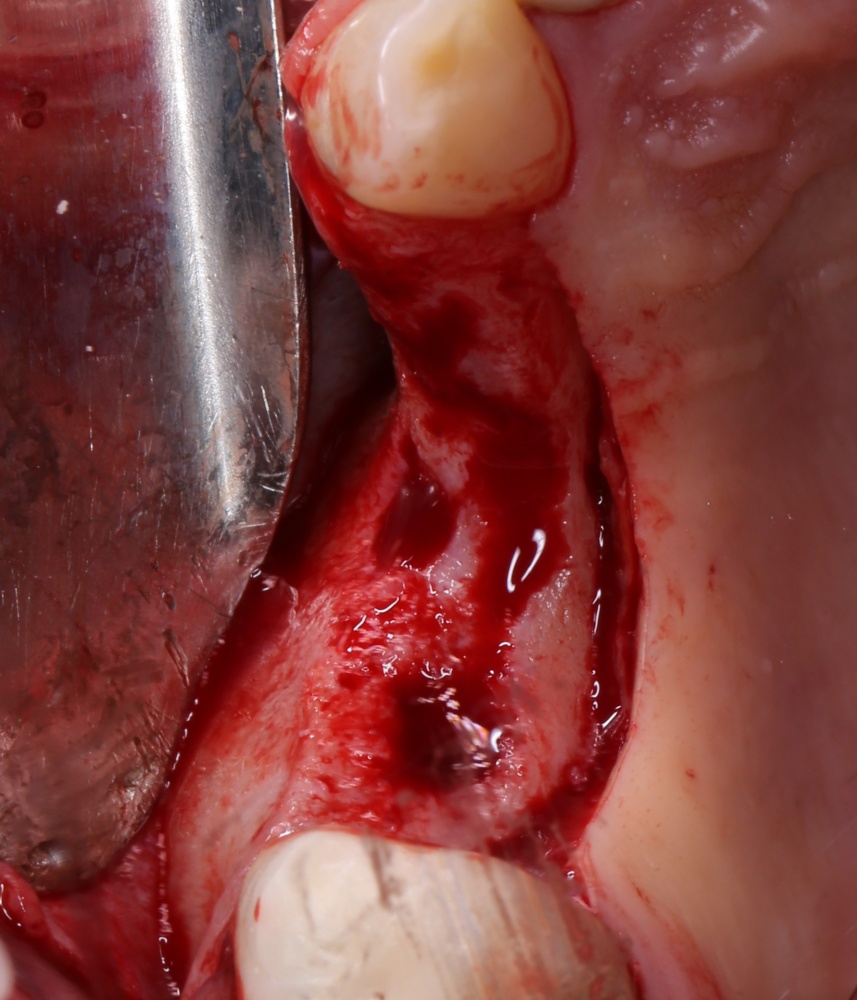

Кстати, обрати внимание на ширину альвеолярного гребня (левая картинка). Она чуть меньше 3 мм. Это объясняет, почему я засомневался в возможности установки имплантатов одновременно с остеопластикой. Понятно и без КЛКТ.

Наперво, мне нужно удалить разрушенный зуб и получить костный аутотрансплантат.

Для получения костного блока, мы открываем донорскую зону, наружную косую линию нижней челюсти.